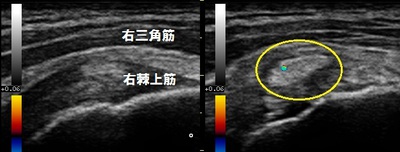

右肩 正常画像 左肩 患部

坂戸市 60代男性。 眠れないほどの左肩の痛み、 棘上筋内石灰沈着炎。

超音波検査をしたところ、左棘上筋の中に石灰が沈着していて右と比較するとかなり腫れている様子が認め

られました(右画像の丸の囲み)。